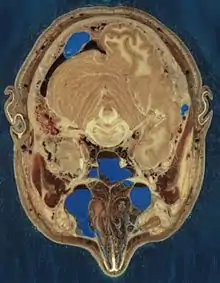

The Visible Human Project is an effort to create a detailed data set of cross-sectional photographs of the human body, in order to facilitate anatomy visualization applications. It is used as a tool for the progression of medical findings, in which these findings link anatomy to its audiences.[1] A male and a female cadaver were cut into thin slices, which were then photographed and digitized. The project is run by the U.S. National Library of Medicine (NLM) under the direction of Michael J. Ackerman. Planning began in 1986;[2] the data set of the male was completed in November 1994 and the one of the female in November 1995. The project can be viewed today at the NLM in Bethesda, Maryland.[3] There are currently efforts to repeat this project with higher resolution images but only with parts of the body instead of a cadaver.

The male cadaver was encased and frozen in a gelatin and water mixture in order to stabilize the specimen for cutting. The specimen was then "cut" in the axial plane at 1-millimeter intervals. Each of the resulting 1,871 "slices" was photographed in both analog and digital, yielding 15 gigabytes of data. In 2000, the photos were rescanned at a higher resolution, yielding more than 65 gigabytes. The female cadaver was cut into slices at 0.33-millimeter intervals, resulting in some 40 gigabytes of data.

The data are supplemented by axial sections of the whole body obtained by computed tomography, axial sections of the head and neck obtained by magnetic resonance imaging (MRI), and coronal sections of the rest of the body also obtained by MRI.

Freezing caused the brain of the man to be slightly swollen, and his middle ear ossicles were lost during preparation of the slices. Nerves are hard to make out since they have almost the same color as fat, but many have nevertheless been identified. Small blood vessels were collapsed by the freezing process. Tendons are difficult to cut cleanly, and they occasionally smear across the slice surfaces.